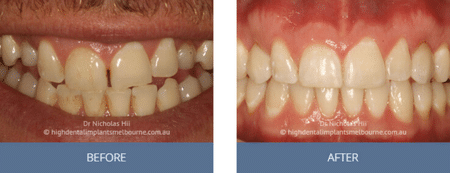

Clinical Before and After Photos

At High Dental, we believe a great smile changes everything. Our Smile Gallery showcases before-and-after images of patients who trusted us with their smiles. From veneers and crowns to full-arch implants, each result is unique — and each started with a consultation. Scroll through and imagine the possibilities for your own smile.

Before & After Disclaimer:

Images are provided for illustrative purposes only. Results shown relate to specific patients and individual outcomes may vary. A consultation is required to determine suitability for treatment.